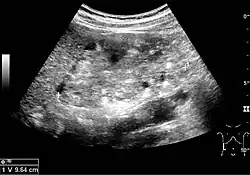

Complex cysts can have membranes dividing the fluid-filled center with internal echoes, calcifications or irregular thickened walls. The complex cyst can be further evaluated with Doppler US, and for Bosniak classification and follow-up of complex cysts, either contrast-enhanced ultrasound (CEUS) or contrast CT is used (Figure 6). The Bosniak classification is divided into four groups going from I, corresponding to a simple cyst, to IV, corresponding to a cyst with solid parts and an 85–100% risk of malignancy.[1] In polycystic kidney disease, multiple cysts of varying size in close contact with each other are seen filling virtually the entire renal region. In advanced stages of this disease, the kidneys are enlarged with a lack of corticomedullary differentiation (Figure 7).[1]

Figure 6. Complex cyst with thickened walls and membranes in the lower pole of an adult kidney. Measurements of kidney length and the complex cyst on the US image are illustrated by '+' and dashed lines.[1] -

Figure 7. Advanced polycystic kidney disease with multiple cysts.[1]